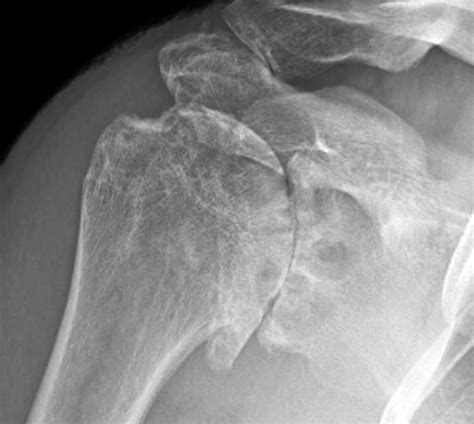

Diagnosing Post Traumatic Arthritis usually involves a combination of clinical history and imaging. A physician will review your history of past injuries and order X-rays to check for joint space narrowing or bone spurs. In more complex cases, an MRI may be requested to visualize the soft tissues and determine the extent of current cartilage damage.

• post traumatic shoulder arthritis